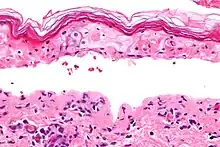

Characteristic skin loss of toxic epidermal necrolysis

Histology

Definitive diagnosis of TEN often requires biopsy confirmation. Histologically, early TEN shows scattered necrotic keratinocytes. In more advanced TEN, full thickness epidermal necrosis is visualized, with a subepidermal split, and scant inflammatory infiltrate in the papillary dermis. Epidermal necrosis found on histology is a sensitive but nonspecific finding for TEN.[7]